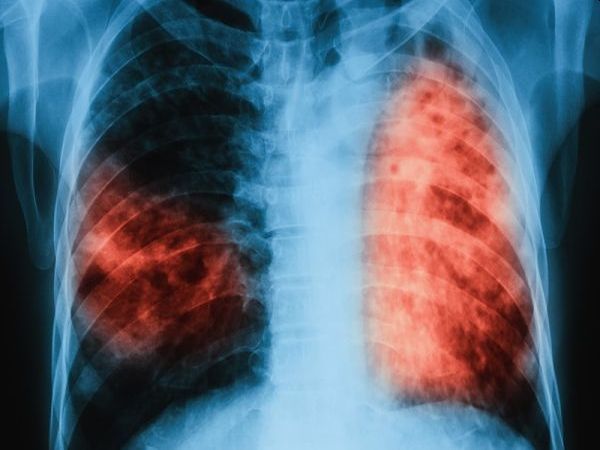

В България след 1998 г. се наблюдава трайна тенденция на намаляване на заболяемостта от туберкулоза – от 49,9 заболели на 100 000 население през 1998 г. на 13,7 заболели на 100 000 през 2024 г., сочи статистиката. Броят на регистрираните случаи на туберкулоза е далеч по-голям при възрастните, отколкото при децата, показват още данните. В детска възраст за периода 2015-2024 г. относителният дял на заболелите от туберкулоза варира между 3 и 10,2% от общия брой случаи в страната. За този период заболяемостта в детска възраст отчита трикратен спад: от 14,1 случая на 100 000 през 2015 г. на 4,1 случая на 100 000 население през 2024 г.

По отношение на излекуваните от туберкулоза лица, наблюдаваната тенденция в страната за периода 2015-2024 г. е низходяща, отчитат здравните власти. Според тях част от проблема е в недостатъчното прилагане на т. нар. „подкрепящи мерки“, като придружаване на лицето до лечебното заведение и други съвместни дейности на регионалните здравни инспекции, неправителствени организации, здравни медиатори и др. за осигуряване на придържане към лечението по време на продължителната фаза. Вероятна причина за отчитания спад са и свързаните с епидемичното разпространение на COVID-19 последици, довели до късно диагностициране на тежки форми на туберкулоза, смятат от МЗ.

През 2024 г. относителният дял на откритите и регистрирани случаи с мултирезистентна туберкулоза се запазва същия както и през 2023 г. – 2,9%, показват още данните на Здравното ведомство.

След 2016 г. в детска възраст не са регистрирани случаи на мултирезистентна туберкулоза, отчитат от там.

По отношение на относителен дял на успешно лекуваните случаи на мултирезистентна туберкулоза, от 2022 г. в страната се отчита нарастване на излекуваните или на завършилите лечение лица с резистентна туберкулоза. От регистрираните през 2023 г. 11 лица, през 2024 г. 8 са успешно завършили лечение.

По отношение на брой лабораторно потвърдени пациенти с мултирезистентна туберкулоза, включени на лечение с противотуберкулозни лекарствени препарати от втори ред, обхванатите лица са съответно през 2021 г. – 20 лица, 2022 г. – 18 лица, 2023 г. – 16 лица и 2024 г. – 14 лица. От ведомството обаче отбелязват, че не всички лица с резистентна туберкулоза са включени на лечение с лекарствени продукти от втори ред.

Цел на програмата е намаляването на заболеваемостта и смъртността от туберкулоза у нас. За постигането й МЗ е определило мерки в шестте приоритетни области, чиято идея е да постигнат съответствие със Стратегията на СЗО за край на туберкулозата до 2030 г.